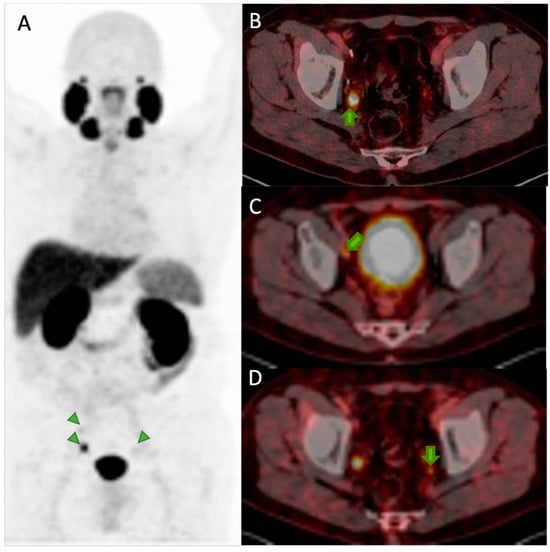

6.3. Detection of Biochemical Recurrence

7.1. 177Lu-PSMA